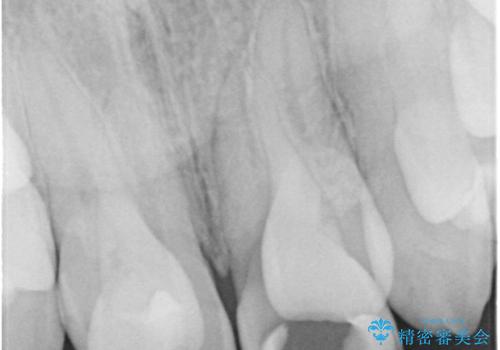

精査したところ、う蝕により歯の内側から黒くなっていました。

根管治療後、セラミッククラウンによる補綴を行いました。

※う蝕が大きく健全歯質が非常に薄いため、長期的予後に関しては不明であることをご理解頂いた上で治療を行いました。

- 根管治療により痛みや腫れがひかない事や、術後に痛みや腫れが生じる事、治療によるファイル破折やパーフォレーションなどの偶発症、術後の歯根破折を生じる可能性もあります